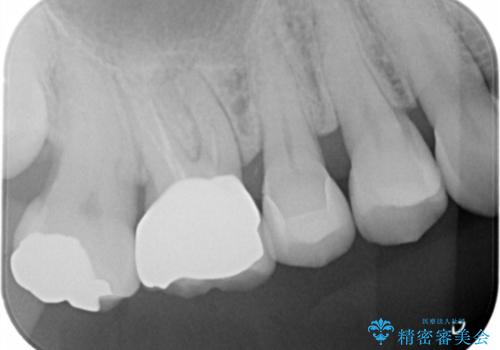

セラミックインレーのやりかえ

- セラミックの詰め物が割れたとの事で来院。

セラミックの詰め物を外して新しくセラミックインレーでやりかえを行いました。

セラミックインレーを外したところ、中にう蝕はありませんでした。

セラミックの詰め物をする事で何年か後に何かしらのエラー(割れる、外れるなど)があった場合、二次的な被害が少ない(う蝕になっていない)のもセラミック治療の特徴です。

歯質とセラミックの間に隙間が生じないので細菌が入り込まないです。